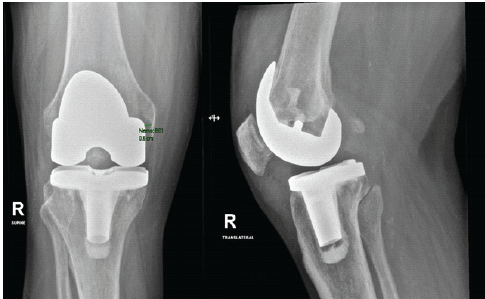

Postoperatively, he developed fever, abdominal pain, and diarrhea then later diagnosed as having Pseudomonas colitis induced by C difficile, attributed to long-term broad-spectrum antibiotic exposure. Managed by modifying his regimen to oral vancomycin, levofloxacin, and linezolid after infectious disease consultation. Despite systemic complications, the right knee remained stable, with preserved extension and flexion up to 90°. After stabilization, he underwent second-stage complex revision TKA (Fig. 6).

Figure 6. Right knee after second-stage revision total knee arthroplasty. Anteroposterior and lateral radiographs demonstrating successful second-stage revision with stemmed prosthetic components following eradication of infection.

Intraoperatively, the surgical field was clean, and the spacer was removed with minimal bone loss. Copious lavage was performed. Definitive components (Johnson and Johnson Attune system, femur size 5, tibia size 4 with stem, liner 5×7) were implanted. The medial and lateral collateral ligaments were stable, no patellofemoral maltracking was observed, and the intraoperative range was full extension and flexion up to 120°. Closure was completed in layers, and the distal neurovascular status was intact. Postoperatively, his vital signs were stable, pain was controlled, and the diarrhea gradually improved. He was discharged with a multidisciplinary home health plan, including orthopedic follow-up, weekly laboratories, and daily physiotherapy (Table 1).